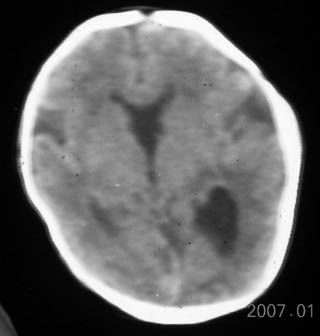

透明隔缺如

透明隔缺如。

这是一个早产儿(大约34周左右)的片子,可以是透明隔缺如,但往往是错误的。

视-隔发育不良:视-隔发育不良是罕见的中线结构前部畸形,主要特征为透明隔缺如,一般常见于垂体性侏儒症。ct表现为正常的透明隔缺如,双侧侧脑室前角及体部融合为一单脑室,侧脑室及第三脑室中度扩大,侧脑室前角在轴位像上呈反三角形,胼胝体压部变薄。约半数患者还伴有其它脑裂畸形改变。

胼胝体发育不全:胼胝体发育不全病因未完全确定,与遗传因素、母体感染或血管因素有关。胼胝体发育不全还可合并半球间裂囊肿、脂肪瘤、透明隔发育不全等。ct表现:半球间裂过深,第三脑室向前上移位,两侧侧脑室扩大,体部分离,呈反“八”字型或平行状。可伴随脑裂畸形、巨脑回、半脑间裂、蛛网膜囊肿及透明隔缺如等

透明隔缺如,支持。